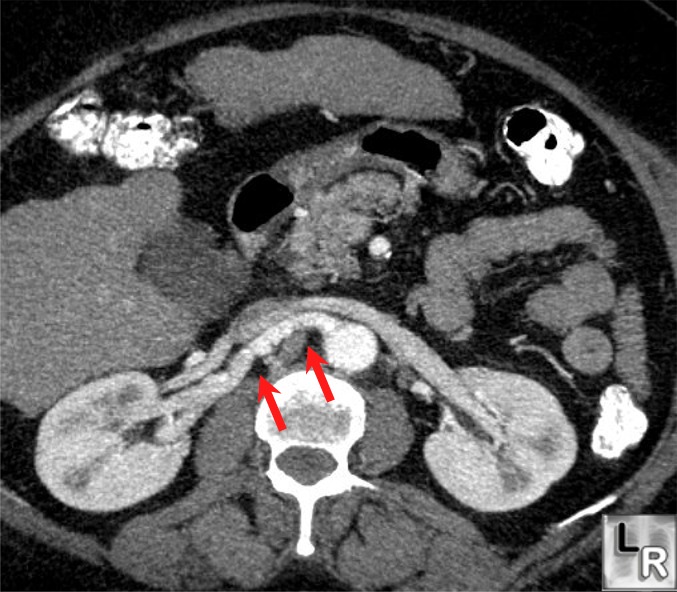

Arrows showing aneurysmal dilation, stenosis and beading of main and Beading Arteries Radiology Segmental arterial mediolysis (sam) is a rare noninflammatory vasculopathy that tends to affect the renal, mesenteric, and iliac arteries [1]. It is often characterized by. Our recent pathological study examining large intracranial arteries showed that intimal calcification existed in advanced. Ct and mri are widely. Comprehensive imaging of a patient with recent stroke depicting left mca stenosis. The cerebral arteries. Beading Arteries Radiology.